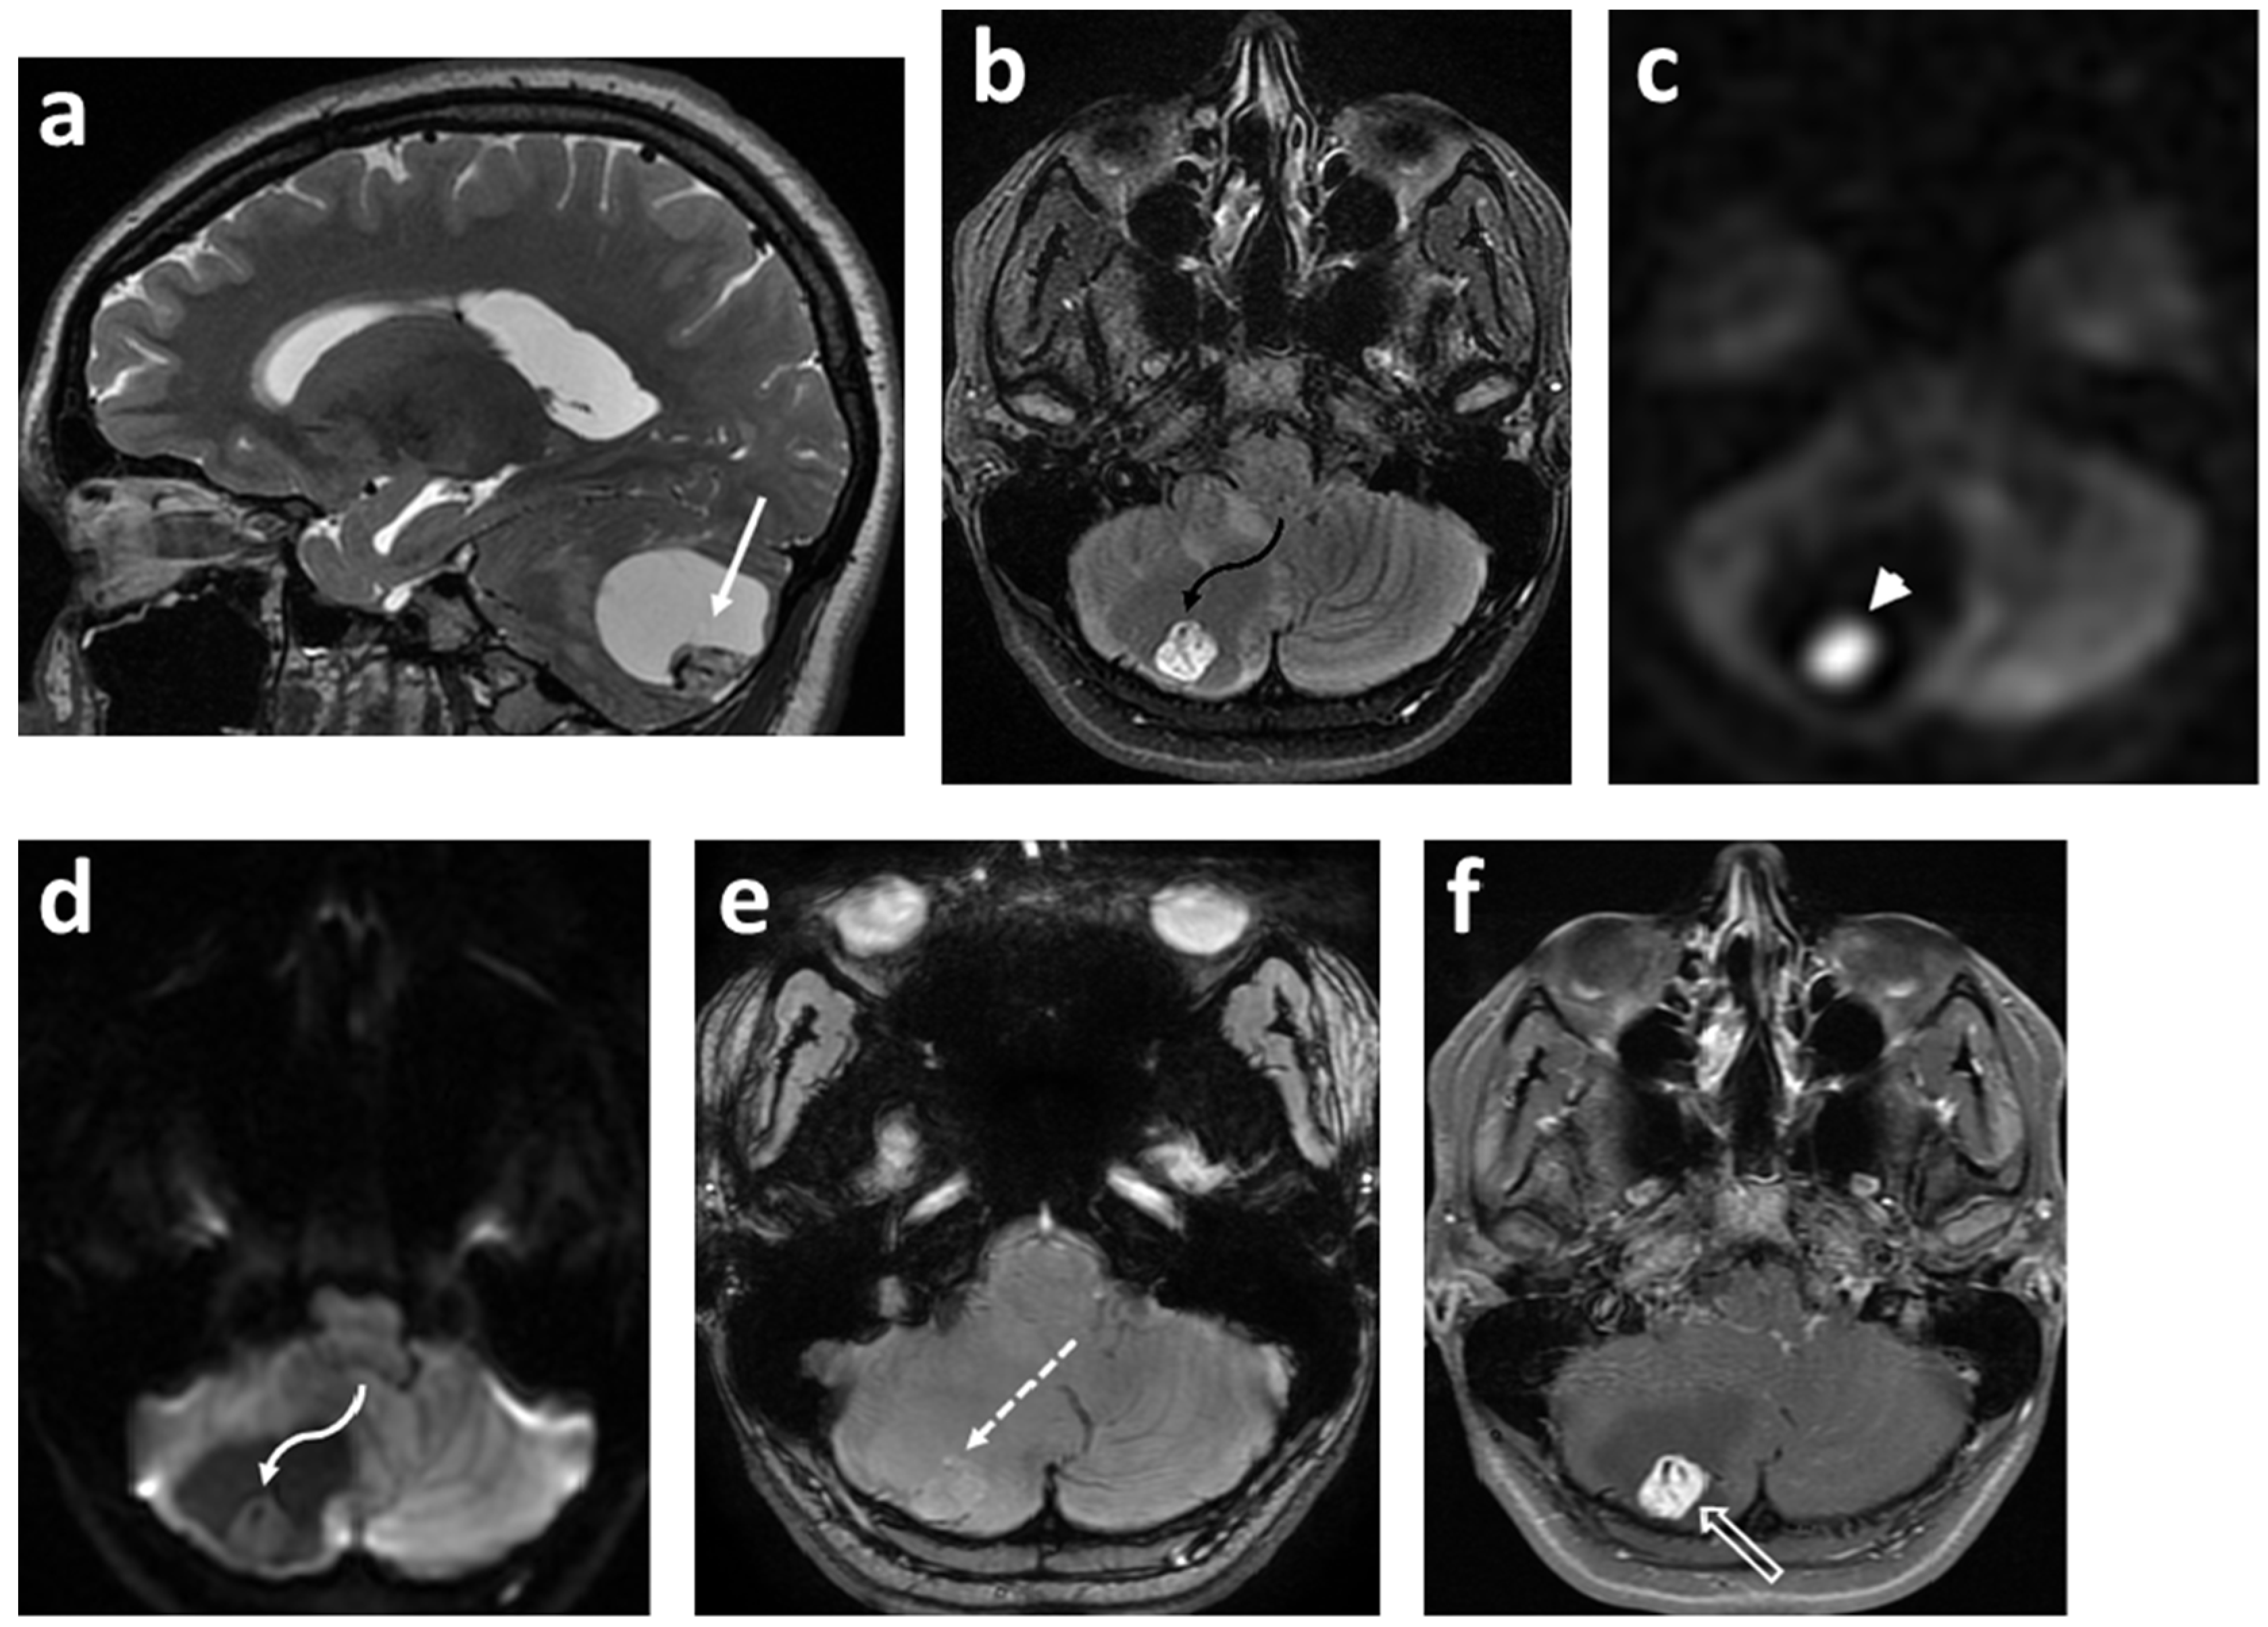

- Morana, G.; Alves, C.A.; Tortora, D.; Severino, M.; Nozza, P.; Cama, A.; Ravegnani, M.; D’Apolito, G.; Raso, A.; Milanaccio, C.; et al. Added value of diffusion weighted imaging in pediatric central nervous system embryonal tumors surveillance. Oncotarget 2017, 8, 60401–60413. [Google Scholar] [CrossRef]

- Shih, R.Y.; Koeller, K.K. Embryonal Tumors of the Central Nervous System: From the Radiologic Pathology Archives. Radio Graph. 2018, 38, 525–541. [Google Scholar] [CrossRef]

- Pierce, T.; Kranz, P.G.; Roth, C.; Leong, D.; Wei, P.; Provenzale, J.M. Use of Apparent Diffusion Coefficient Values for Diagnosis of Pediatric Posterior Fossa Tumors. Neuroradiol. J. 2014, 27, 233–244. [Google Scholar] [CrossRef]

- Jaremko, J.; Jans, L.; Coleman, L.; Ditchfield, M. Value and limitations of diffusion-weighted imaging in grading and diagnosis of pediatric posterior fossa tumors. Am. J. Neuroradiol. 2010, 31, 1613–1616. [Google Scholar] [CrossRef]